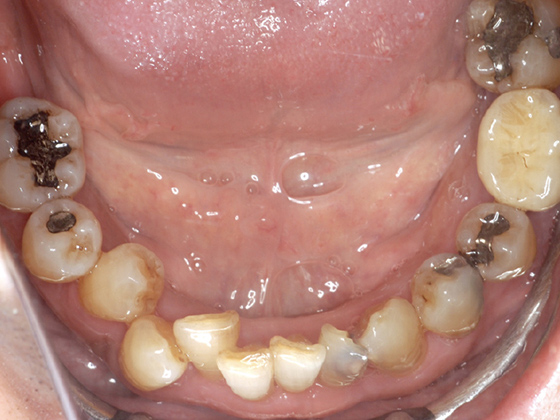

治療前

全体的に重度の歯周病でグラグラの状態です。下はオールオン4で、上に関しては骨の状態的にオールオン4が不可能なため、サイナスリフトとインプラントで治療をすることにしました。